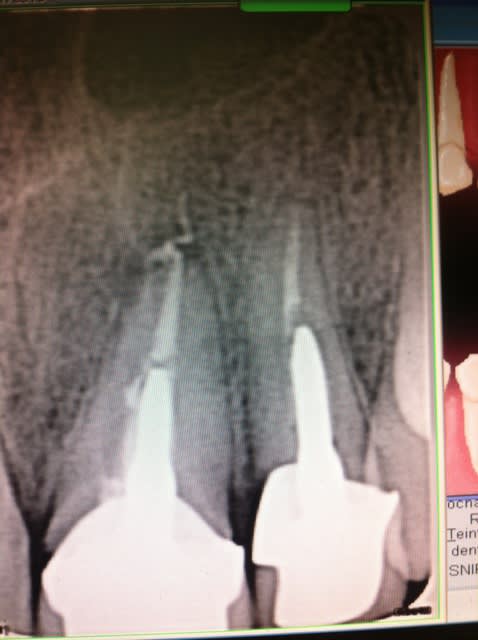

Ras à la rétro sauf un petit dépassement sur 21. Gencive tuméfiée, violacée en vestibulaire de 21-22. La 21 a déjà eu un Rte il y a 4 ans.

Rien au sondage, mais en regardant de plus prés la rétro, je suspecte un trait de fracture en distal de 22...

Mis sous Antibio, plus de signe clinique. Prescription de cone Beam et surprise, belle image...

Que penses tu de la taille de la lésion?

Elle est quand même volumineuse. Tu penses qu'en greffe d'apposition pourrait être envisageable?